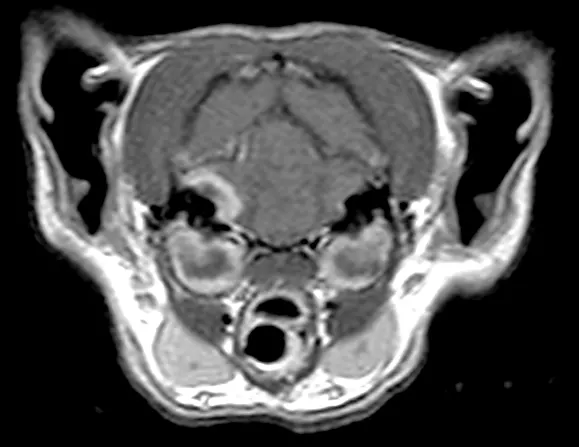

Figure 3

MRI of a patient with bilateral otitis media/interna. There is translocation of the infection across the bone invading the right side of the meninges.